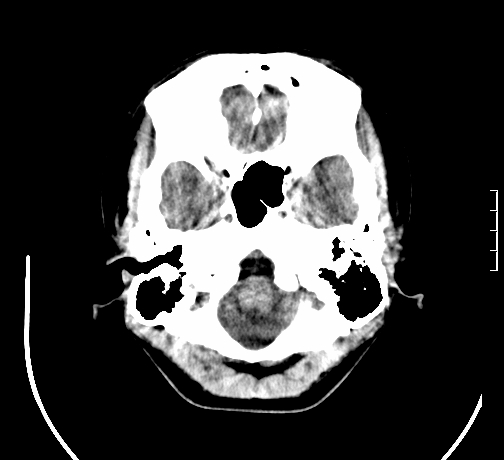

女,28岁,幼时有癫痫,常有发作,服药后可几月不发作,走路不稳3-4月,加重一月。

小脑发育畸形?

小脑萎缩。

考虑小脑发育不良,建议mri检查。

患者出现走路不稳是近几个月的事,而癫痫则有幼时就有,常发,则会常服药,癫痫药可引起小脑综合症,小脑萎缩,而小脑发育不良的主要症状不是癫痫

考虑癫痫,长期间断发服抗癫药,导致小脑综合症,小脑萎缩

不知现在还有没有癫痫,应该另有致痫灶,进一步检查。

考虑小脑发育不良伴小脑萎缩,建议mri检查。

小脑萎缩,原因待查,建议mri检查。

考虑小脑发育不良伴小脑萎缩,建议mri检查

考虑药物性小脑萎缩